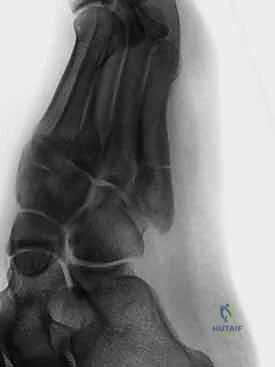

لنبداً بتحديد ما نتعامل معه بالضبط. كسر جونز هو إصابة حادة تحدث في العظمة الخامسة من مشط القدم (Metatarsal Bone)، وهي العظمة الطويلة التي تقع على الحافة الخارجية للقدم وترتبط بإصبع القدم الصغير. سُمي هذا الكسر بهذا الاسم نسبة إلى جراح العظام البريطاني السير "روبرت جونز" الذي وصفه لأول مرة في عام 1902 بعد أن أصيب هو شخصياً به أثناء الرقص!

السبب الذي يجعل كسر جونز سيئ السمعة في عالم جراحة العظام هو موقعه الدقيق. يحدث الكسر في منطقة تُعرف باسم المشاش (Metaphyseal-Diaphyseal Junction). هذه المنطقة تحديداً تعاني من ضعف شديد في الإمداد الدموي، وتُعرف طبياً باسم منطقة ضعف التروية (Watershed Area). وكما نعلم، الدم هو الناقل الأساسي للأكسجين والعناصر الغذائية والخلايا البانية للعظم؛ وبدون تدفق دموي كافٍ، تصبح عملية التئام الكسر بطيئة للغاية، وترتفع احتمالات عدم الالتئام (Non-union) أو تأخر الالتئام (Delayed union) بشكل كبير إذا لم يتم التدخل بشكل صحيح.

من الضروري جداً التفريق بين كسر جونز وأنواع الكسور الأخرى التي تصيب نفس العظمة، وهنا تتجلى خبرة الأستاذ الدكتور محمد هطيف في التشخيص الدقيق:

1. الكسر القلعي (Avulsion Fracture): يحدث في قاعدة العظمة (أقرب للكعب) وغالباً ما يلتئم بسهولة بالجبس.

2. كسر جونز (Jones Fracture): يحدث في منطقة ضعف التروية الدموية، ويحتاج غالباً لتدخل جراحي.

3. الكسر الإجهادي (Stress Fracture): يحدث في منتصف العظمة نتيجة الإجهاد المتكرر، ويكون علاجه معقداً أيضاً.

- التصوير بالأشعة السينية (X-rays): هي الخطوة الأولى والأساسية. يتم أخذ صور بأوضاع مختلفة (أمامية، جانبية، ومائلة) لتحديد موقع الكسر وشكله بدقة.

- التصوير بالرنين المغناطيسي (MRI) أو الأشعة المقطعية (CT Scan): في بعض الحالات المعقدة، أو إذا كان الكسر إجهادياً قديماً ولم يظهر بوضوح في الأشعة العادية، يطلب الدكتور هطيف هذه الفحوصات المتقدمة لتقييم مدى تلف العظم والأنسجة المحيطة.